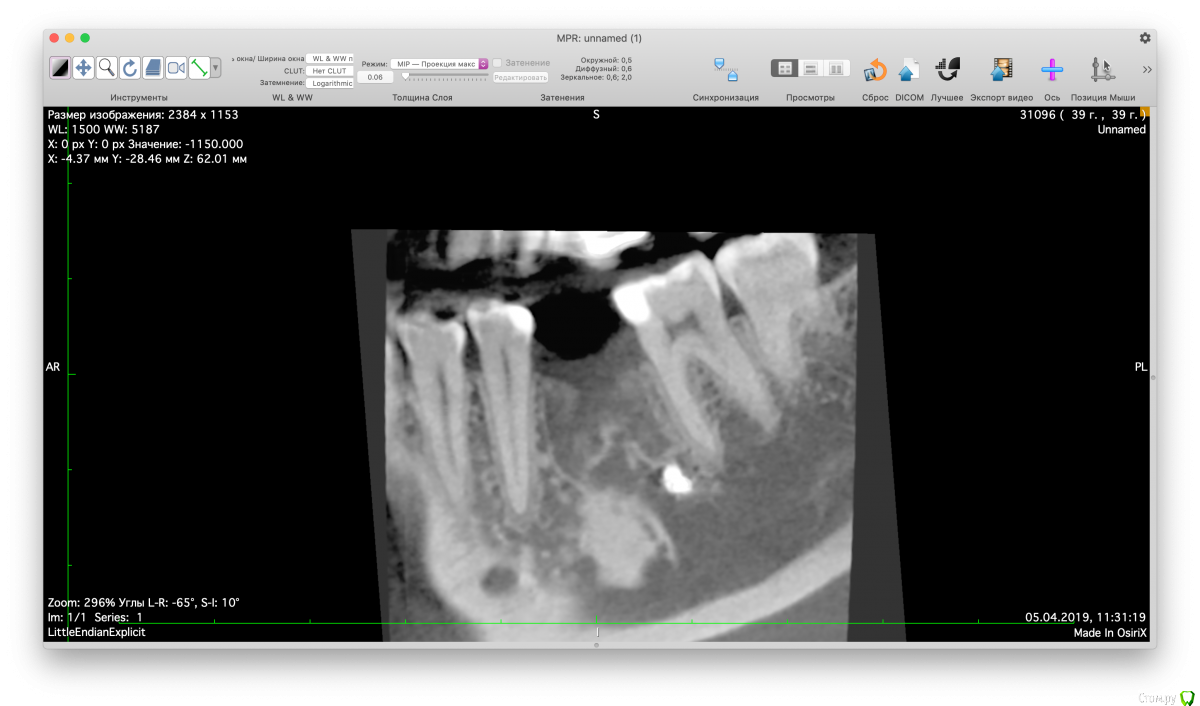

Valerkaa Опубликовано 15 мая, 2019 Поделиться Опубликовано 15 мая, 2019 Добрый день, коллеги. Только начинаю свою работу в сфере имплантации. Планируется имплантация в области отсутствующего 3.6, меня смущает наличие ранее выведенного пломбировочного материала. Понимаю, что при формировании ложа под имплантат материал фрезой не удалится, смущает просто само наличие материала вблизи будущего имплантата. Доставать или оставить все как есть? Заранее спасибо. Ссылка на комментарий

Дмитрий Л. Опубликовано 15 мая, 2019 Поделиться Опубликовано 15 мая, 2019 Имплант должен стать мезиальнее. 1 Ссылка на комментарий